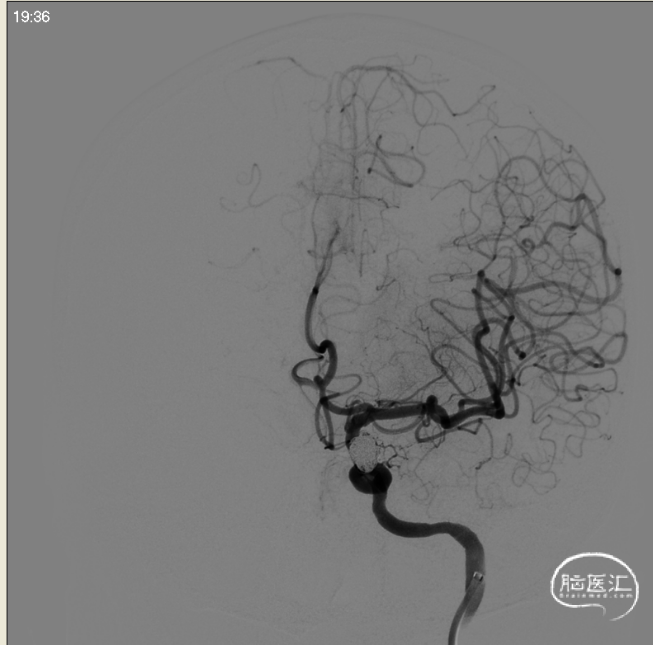

术前左侧侧位

术前左侧正位

术前右侧正位

术前右侧侧位

术前工作位

左侧3D

右侧3D

取右侧股动脉为穿刺点,Seldinger法穿刺成功后置入6F鞘。行全脑血管造影显示左侧颈内动脉眼动脉段动脉瘤,约10*7mm大小,瘤颈6.1mm。6F 90长鞘+115cm 6F SKATHI中间导管超选至左侧颈内动脉海绵窦段。